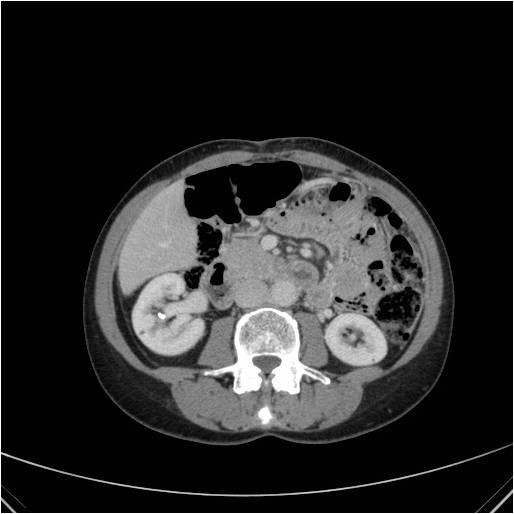

Tomodensitométrie avec injection au temps mixte néphrographique et excrétoire. Visibilité du calcul par transparence au niveau des cavités rénales droites. Opacification mixte du parenchyme rénal et des cavités rénales.